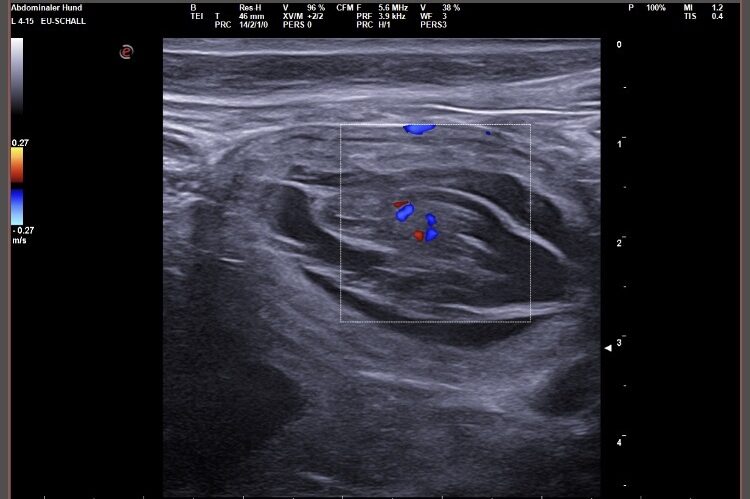

Wir waren erfolgreich und konnten Fruchtanlagen mit schlagenden Herzen sehen. Wir gehen zum aktuellen Zeitpunkt wieder von einem größeren Wurf aus. Daykos und Dorias Rendevouz war also sehr vielversprechend!

Hier zeigen wir euch einige der kleinen gefüllten Fruchtblasen mit Inhalt und schlagenden Herzen. Da wir kurz vor Ostern mit der Geburt rechnen, nennen wir sie „Ostereier“ 🙂